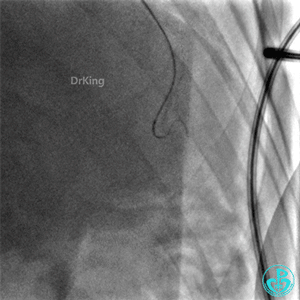

启动Reverse CART,正向2.0×15mm球囊扩张后逆向导丝尝试进入前降支近端真腔。

正向Guidezilla迎合,逆向导丝、微导管进入子导管,正向导丝通过逆向微导管后2.0×15mm球囊扩张闭塞段。